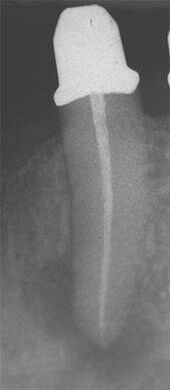

Erfolgreich abgeheilte Entzündung 6 Monate später. Beschwerdefreier Zahn.